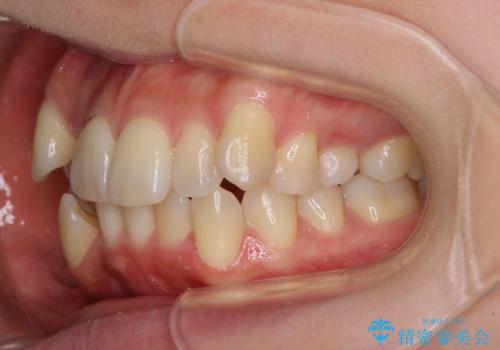

- デコボコの歯列で歯磨きがしにくいことを気にして来院された患者様です。

右側の上下は歯が重なり合って、内側に移動してしまうほどであり、それに伴って正中の位置が右側にずれている状態でした。

上下左右の第一小臼歯4本を抜歯して行うことになりますが、それだけでは咬み合わせの改善や正中位置の改善が困難であると判断されたため、アンカースクリューを用いた補助装置を併用することで、スムーズかつより良い仕上がりを目指すこととしました。